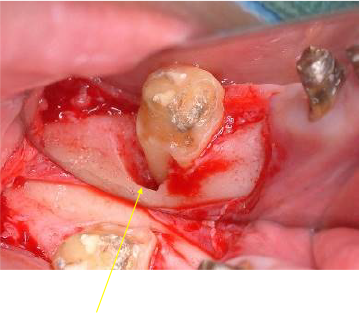

歯肉形成外科の術中所見です。最終的は被せもののイメージを行いながら歯茎と顎の骨の整形を行いました。

歯茎の下の方まで虫歯でしたが歯茎の上までしっかりと健康な歯の部分を出すことができました。